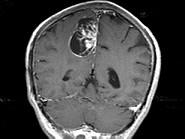

问题 男,68岁,头痛头昏、左侧肢体肌力减退3个月余,请根据所提供图像,选择最可能的诊断()

选项 A.(右顶叶镰旁)恶性脑膜瘤 B.(右顶叶镰旁)胶质瘤 C.(右顶叶镰旁)血管外皮瘤 D.(右顶叶镰旁)脑膜瘤(血管瘤型) E.(右顶叶镰旁)转移瘤

答案 D